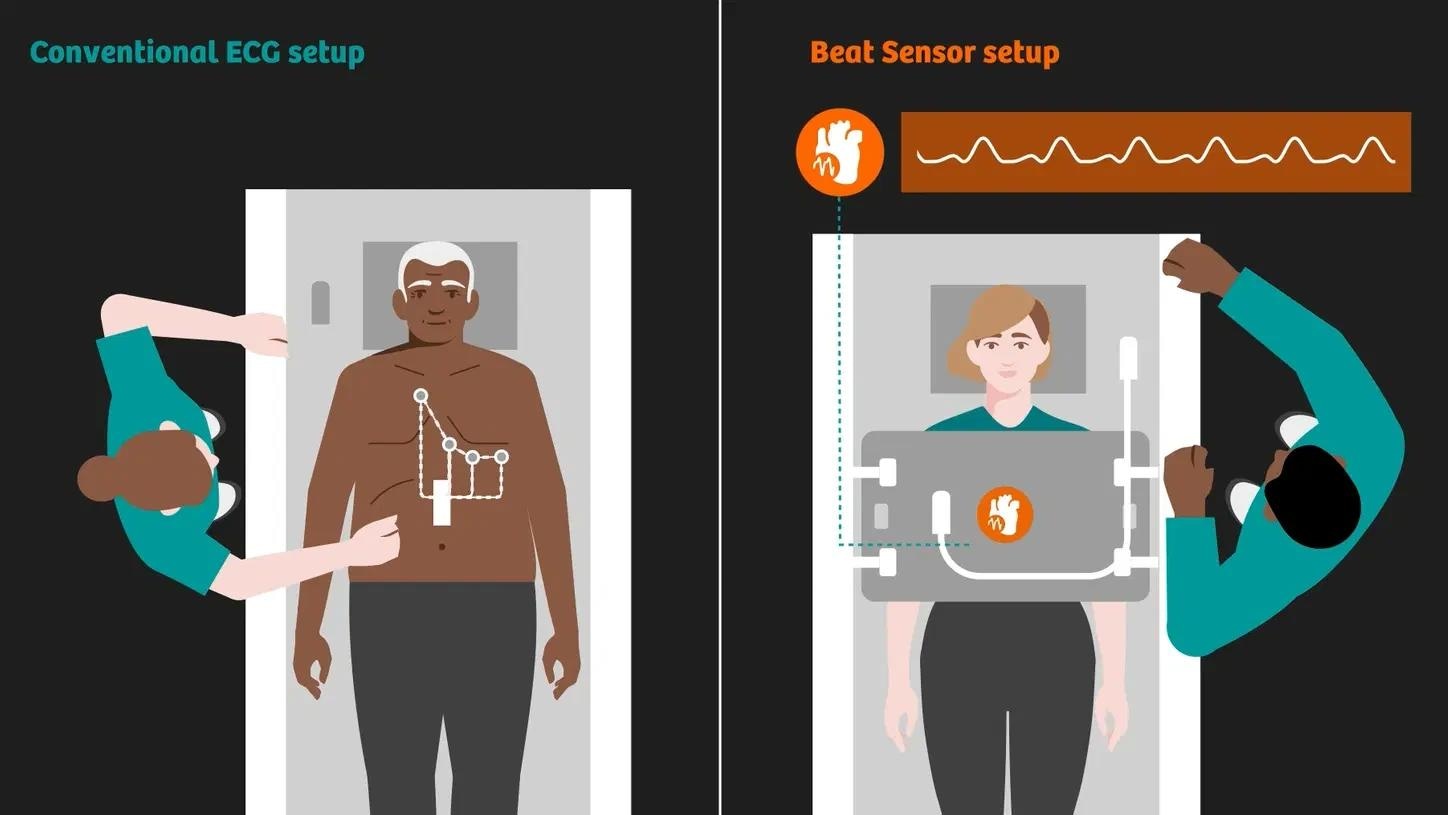

BioMatrix Beat Sensor

Complete cardiac MRI exams without ECG leads. This means faster workflows and increased patient comfort.

BioMatrix Sensors

New BioMatrix Sensors capture cardiac and respiratory movements for improved consistency.